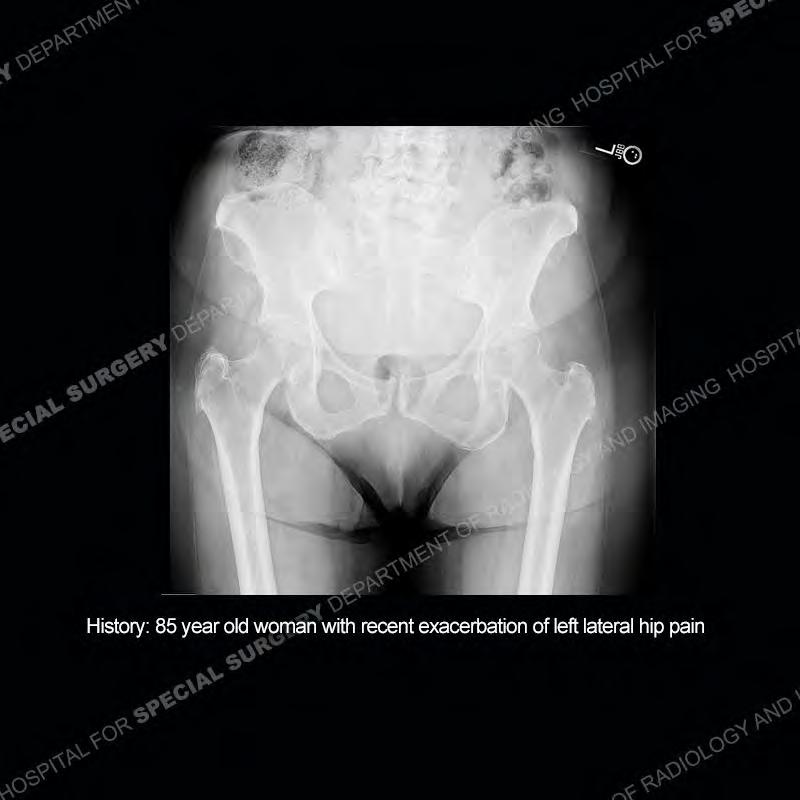

The radiograph is not particularly contributory in this case. The MRI demonstrates markedly abnormal architecture of the gluteus minimus and anterolateral band of the gluteus medius. Portions of the tendons are high signal, portions are highly attenuated, and portions are disrupted. A large, complex fluid collection is present in the adjacent soft tissue.

Diagnosis: Gluteal Tendinosis and Disruption with Complex Trochanteric Bursal Collection